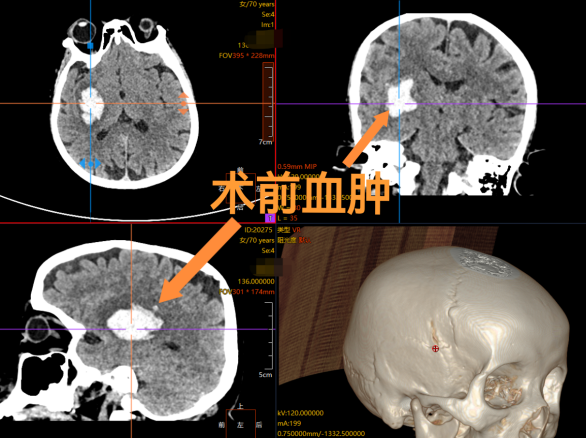

患者焦阿姨(化名)在家中突发左侧肢体完全瘫痪、意识模糊,家属紧急送入我院急诊。经检查,头颅CT显示患者右侧基底节区脑出血,血肿压迫关键神经功能区,随时可能危及生命。基底节区出血手术难度极高,传统开颅创伤大、风险高,而保守治疗可能遗留肢体偏瘫等严重后遗症。经神经外科、急诊医学科、麻醉科多学科团队快速评估,最终决定启用"立体定向机器人辅助血肿清除术"。

在机器人三维定位系统引导下,神经外科蔡璞主任主刀,通过一个不足5mm的颅骨钻孔,将引流管精准置入血肿中心。术中实时影像监测显示,暗红色血性液体被快速清除,受压脑组织即刻得到减压。手术全程不足1小时,出血量5ml,真正实现了"精准打击、最小创伤"。